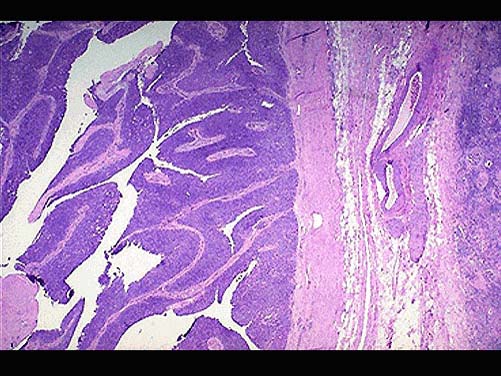

男,65岁。间歇性无痛性肉眼血尿1年。膀胱镜检:膀胱内距输尿管口0.5cm,可见2.5cm×1cm×1cm乳头状肿块,无蒂。静脉肾盂造影可见左肾轻度积水,输尿管全段轻度扩张。行膀胱部分切除后镜检如图所示,下列说法正确的是 ( )

• A.该疾病好发部位为膀胱尖部

• B.该疾病为膀胱透明细胞癌

• C.该疾病手术后不易复发

• D.常见的症状为无痛性血尿

• E.发生在膀胱的肿瘤大部分为良性